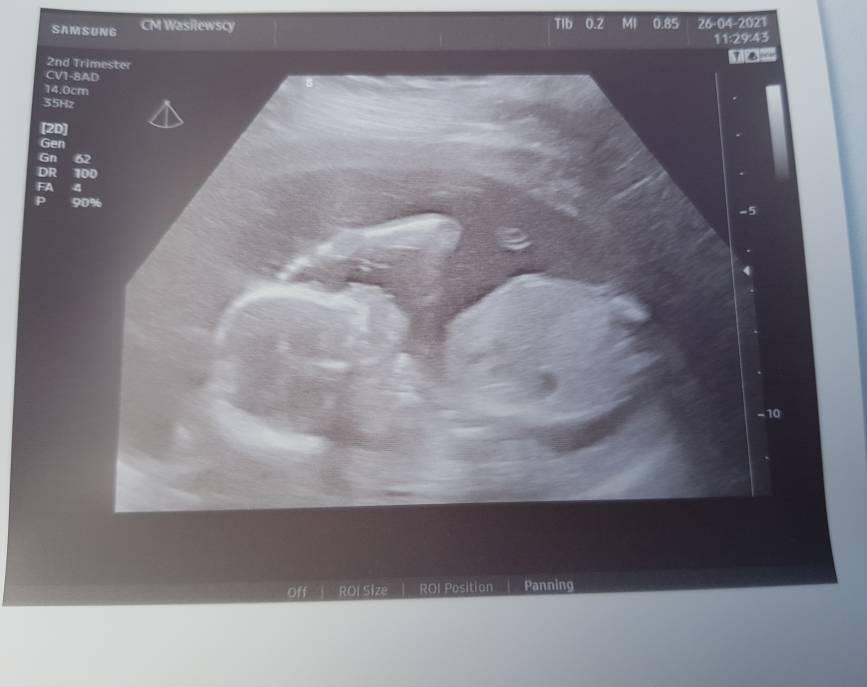

Lekarz potwierdził ostatnio że będzie synek [emoji4]Zobacz załącznik 1266563